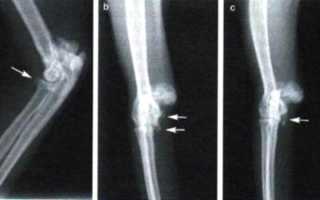

Экзостоз коленного сустава требует отдельного рассмотрения. Как и экзостозы позвоночника, их рост может быть направлен внутрь, что может повредить спинной мозг.

Экзостоз коленного сустава начинается с бедра и разрастается под четырехглавой мышцей, оказывая на нее давление. Это может привести к повреждению мышцы, ее растяжению, а иногда даже к переломам и образованию «новых» суставов.